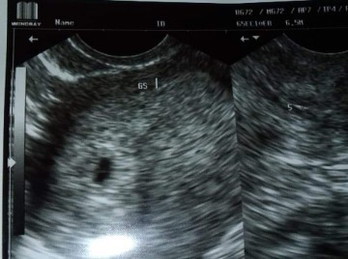

Sino po sa inyo mga momshies nahihirapan matulog yung tipong ramdam mong antok na antok ka tas pag nag try ka matulog parang nakapikit lang tas gising yung diwa😭 ano po pwede gawin? Di po kaya to side effect ng iniinom kong folic acid? 7weeks and 2days pregnant here.😭 help po #firstbaby #1stimemom